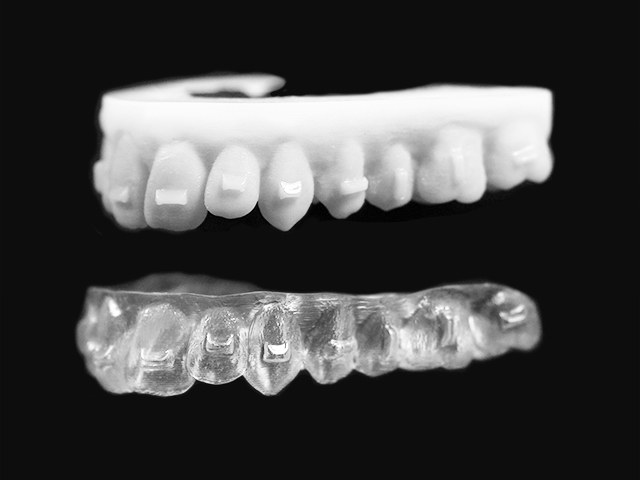

Precision and Predictability: Placing Clear Aligner Attachments with Tetric EvoCeram Aligner

Introduction: Raising the Bar for Attachment Accuracy Invisalign and other clear aligner therapies continue to evolve, with increasing case complexity and more sophisticated treatment goals. As a dental assistant and educator working chairside with general dentists and orthodontists, one of the most impactful clinical procedures I assist with is attachment placement. These composite buttons are … Read more